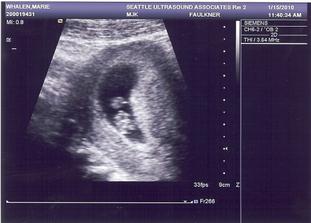

• 15.1.2010 Prvni ultrazvuk odhalil blikajici srdicko, zarodek 7 tydnu stary a vsechno v naprostem poradku.